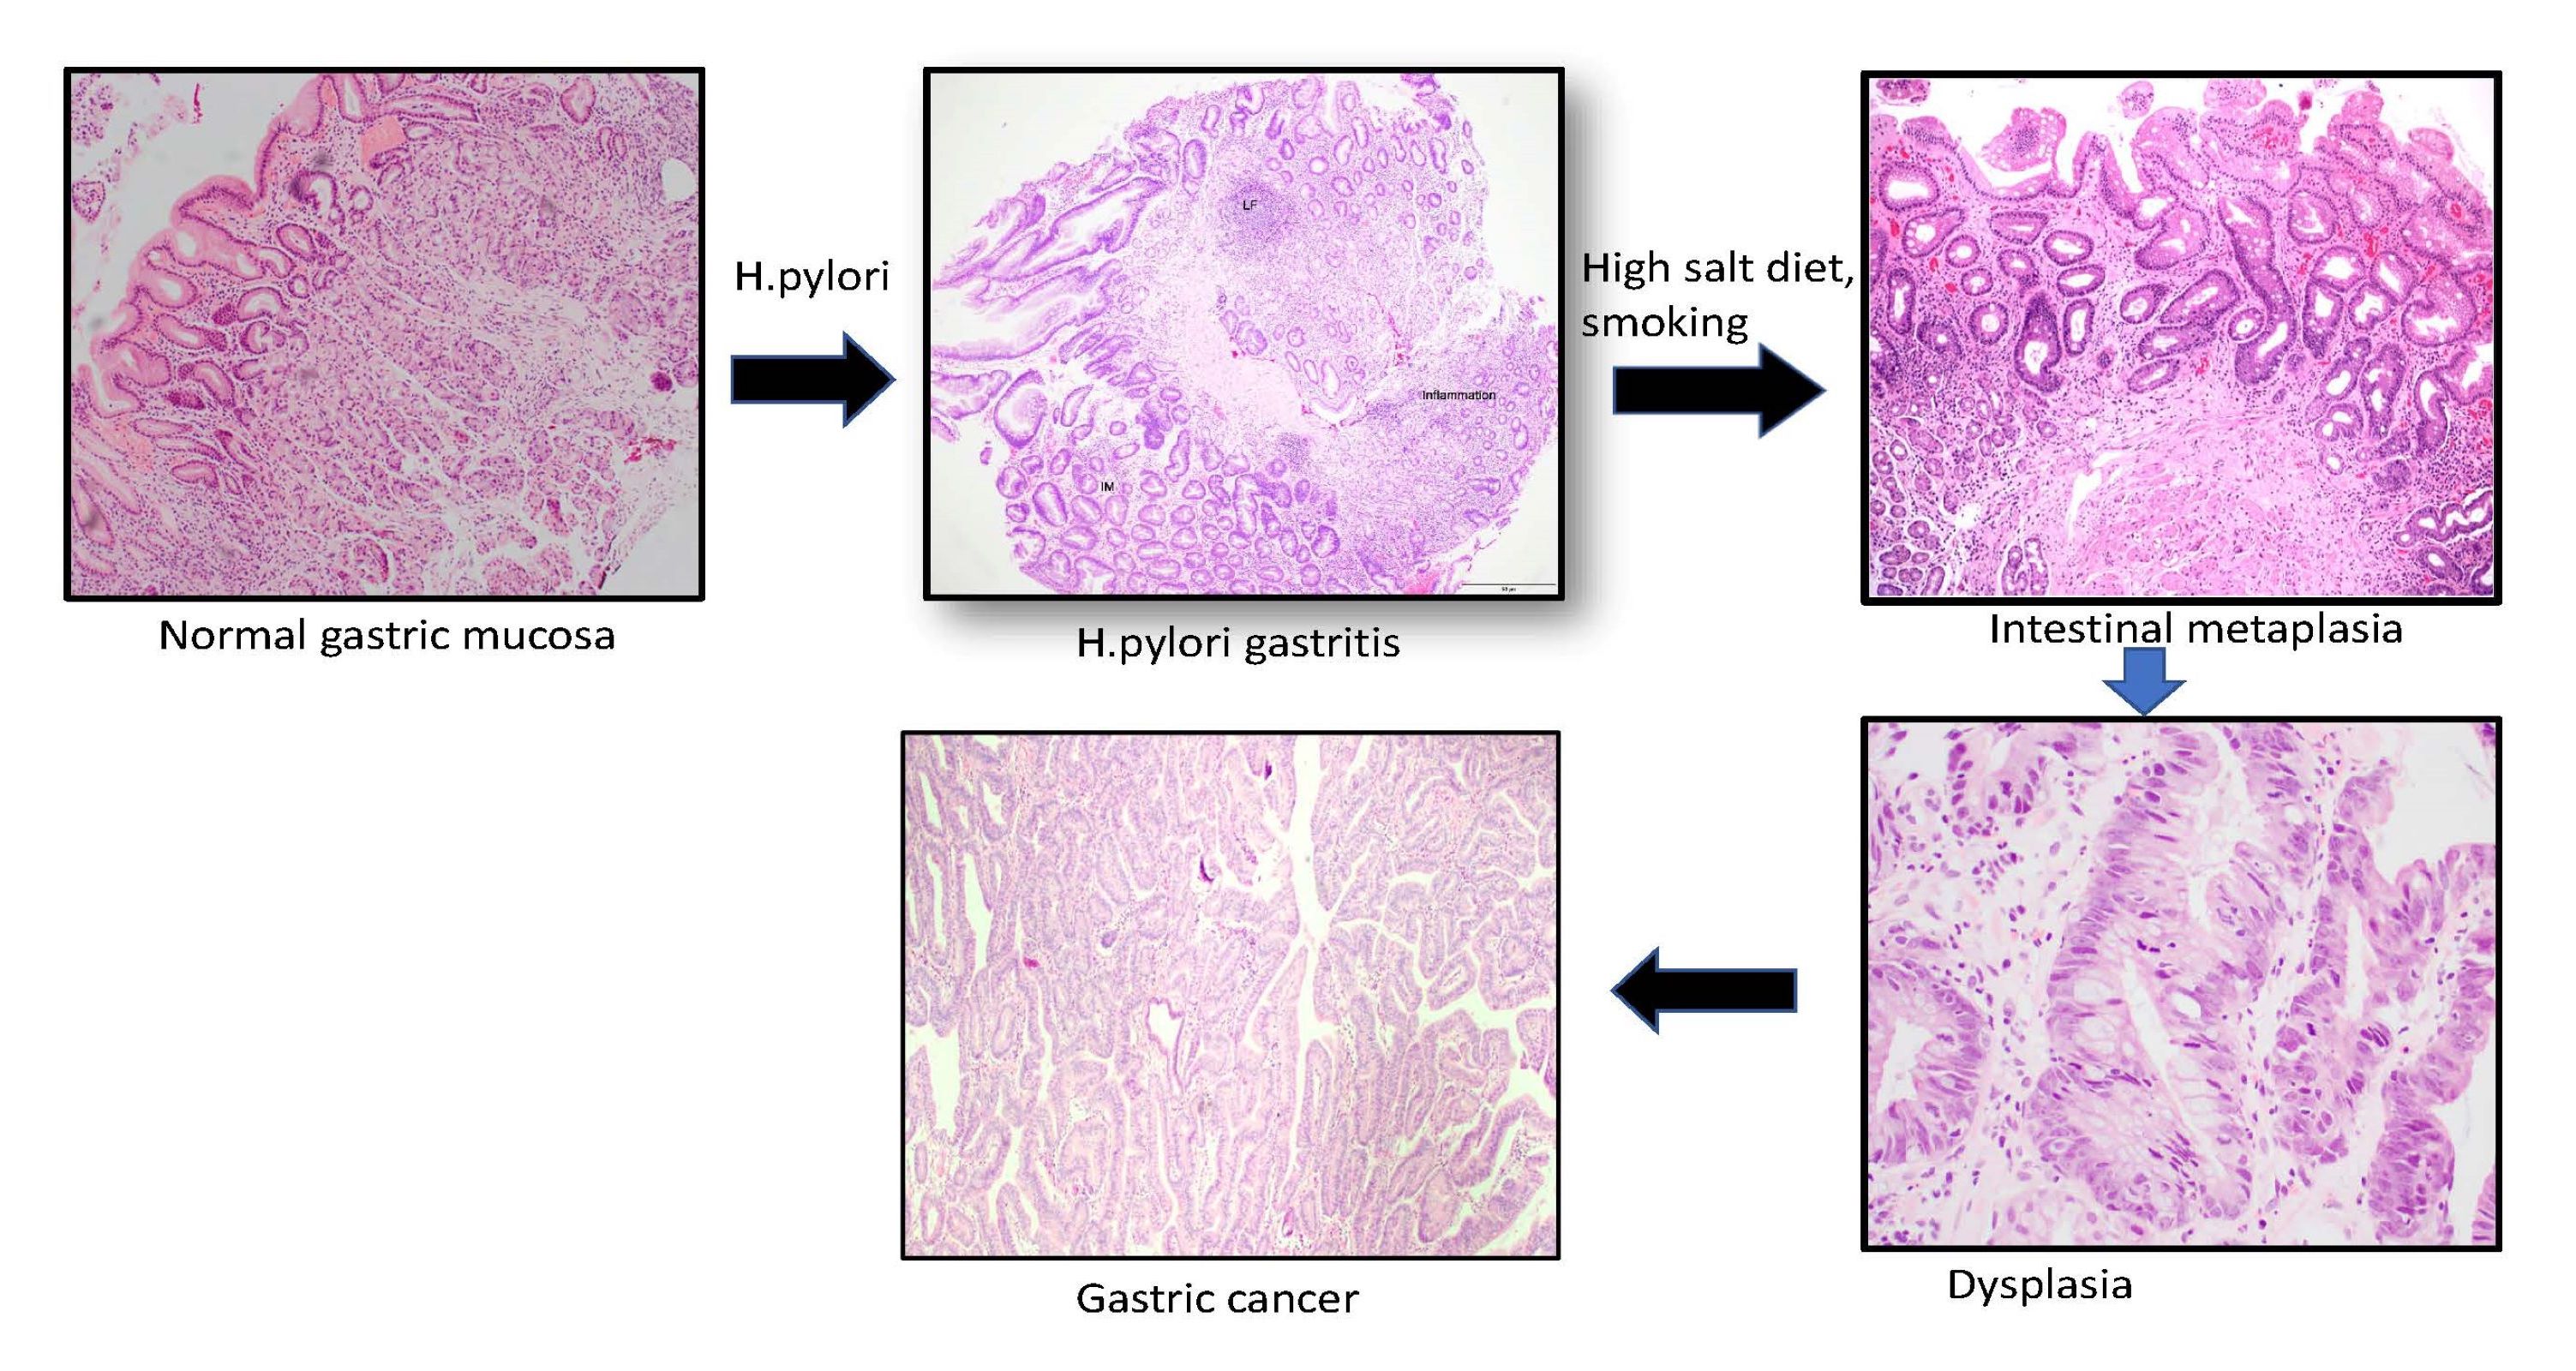

- Intestinal metaplasia results from a distinct interplay between host immune susceptibility, genetic response and environmental exposure; chronic mucosal inflammation leads to gastric atrophy, which leads to replacement of gastric mucosa with intestinal type epithelium

- Helicobacter pylori infection, bile reflux, smoking, high salt intake

- Intestinal metaplasia can be identified by the replacement of gastric columnar mucosa with intestinal type of mucosa comprised of goblet cells, with or without Paneth cells and absorptive brush border

- Usually occurs in a background of chronic gastritis or H. pylori gastritis

- It can be classified as complete (type I) and incomplete (II and III) subtypes

- Complete (type I) intestinal metaplasia (Cancer Res 1999;59:1003):

- Resembles small intestinal mucosa with straight crypt architecture, well formed goblet cells, Paneth cells and absorptive brush border

- Incomplete (type II and III):

- Histologically resembles either small or large intestinal mucosa and shows irregular architecture, variable size goblet cells and columnar mucosa in various stages of differentiation; Paneth cells and absorptive brush border may or may not be seen

- Type III intestinal metaplasia shows highest association with gastric cancer

- Intestinal metaplasia is graded as mild (< 30%), moderate (31 - 60%) and marked (61 - 100%) according to the updated Sydney classification

- Intestinal metaplasia is staged using the OLGA / OLGIM system; it is based on the grades of intestinal metaplasia in the antrum (including incisura) and body

- OLGA / OLGIM stages III and IV are considered as high risk for progression to gastric cancer (Gastrointest Endosc 2010;71:1150)